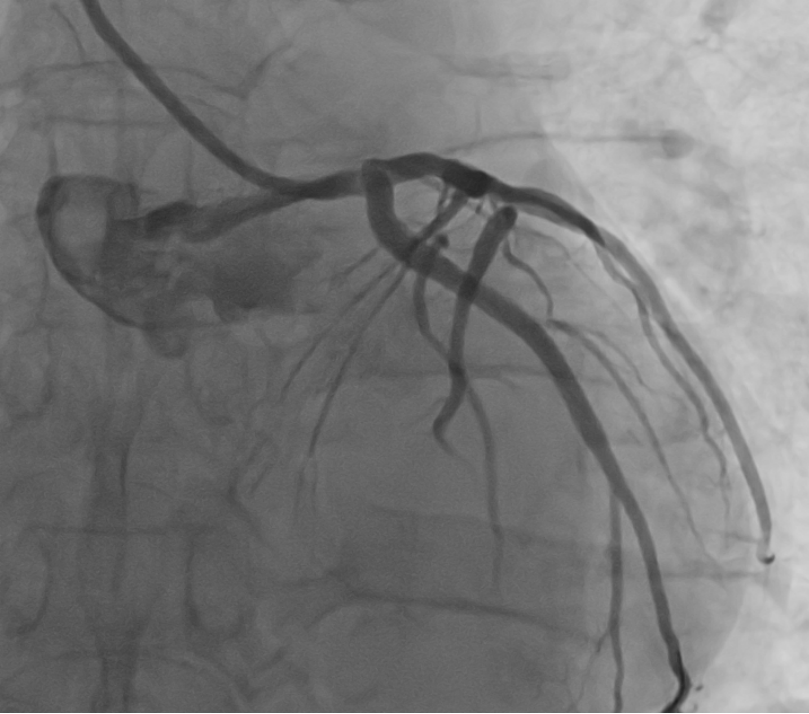

术后冠脉造影,回旋支支架术后未见狭窄患者是一名65岁男性,入院诊断冠心病,不稳定型心绞痛,经术前冠脉CTA评估提示回旋支重度狭窄,进一步行冠脉造影及介入治疗。2月4日,患者完成冠脉造影,结果示双支病变,回旋支重度狭窄,前降支中度狭窄,结果同术前冠脉CTA。经心内科主任医师姚道阔、副主任医师何晓全与主治医师化冰共同讨论,认为该患者符合冠脉介入手术指征,并且符合血管介入控制系统辅助完成冠脉介入手术入组条件,团队决定在血管介入手术控制系统辅助下完成冠脉介入手术。

手术室内,由化冰负责在血管介入控制系统机械臂上安装指引导管、导丝及球囊、支架等手术器械;手术室外,姚道阔操控血管介入控制系统输送器械,并依次对患者靶病变进行球囊扩张及支架植入。经团队紧密配合,血管介入手术控制系统辅助下,患者回旋支狭窄病变成功植入1枚支架,术后造影显示原回旋支狭窄病变完全消失,效果非常满意,手术仅用时20分钟,取得圆满成功。